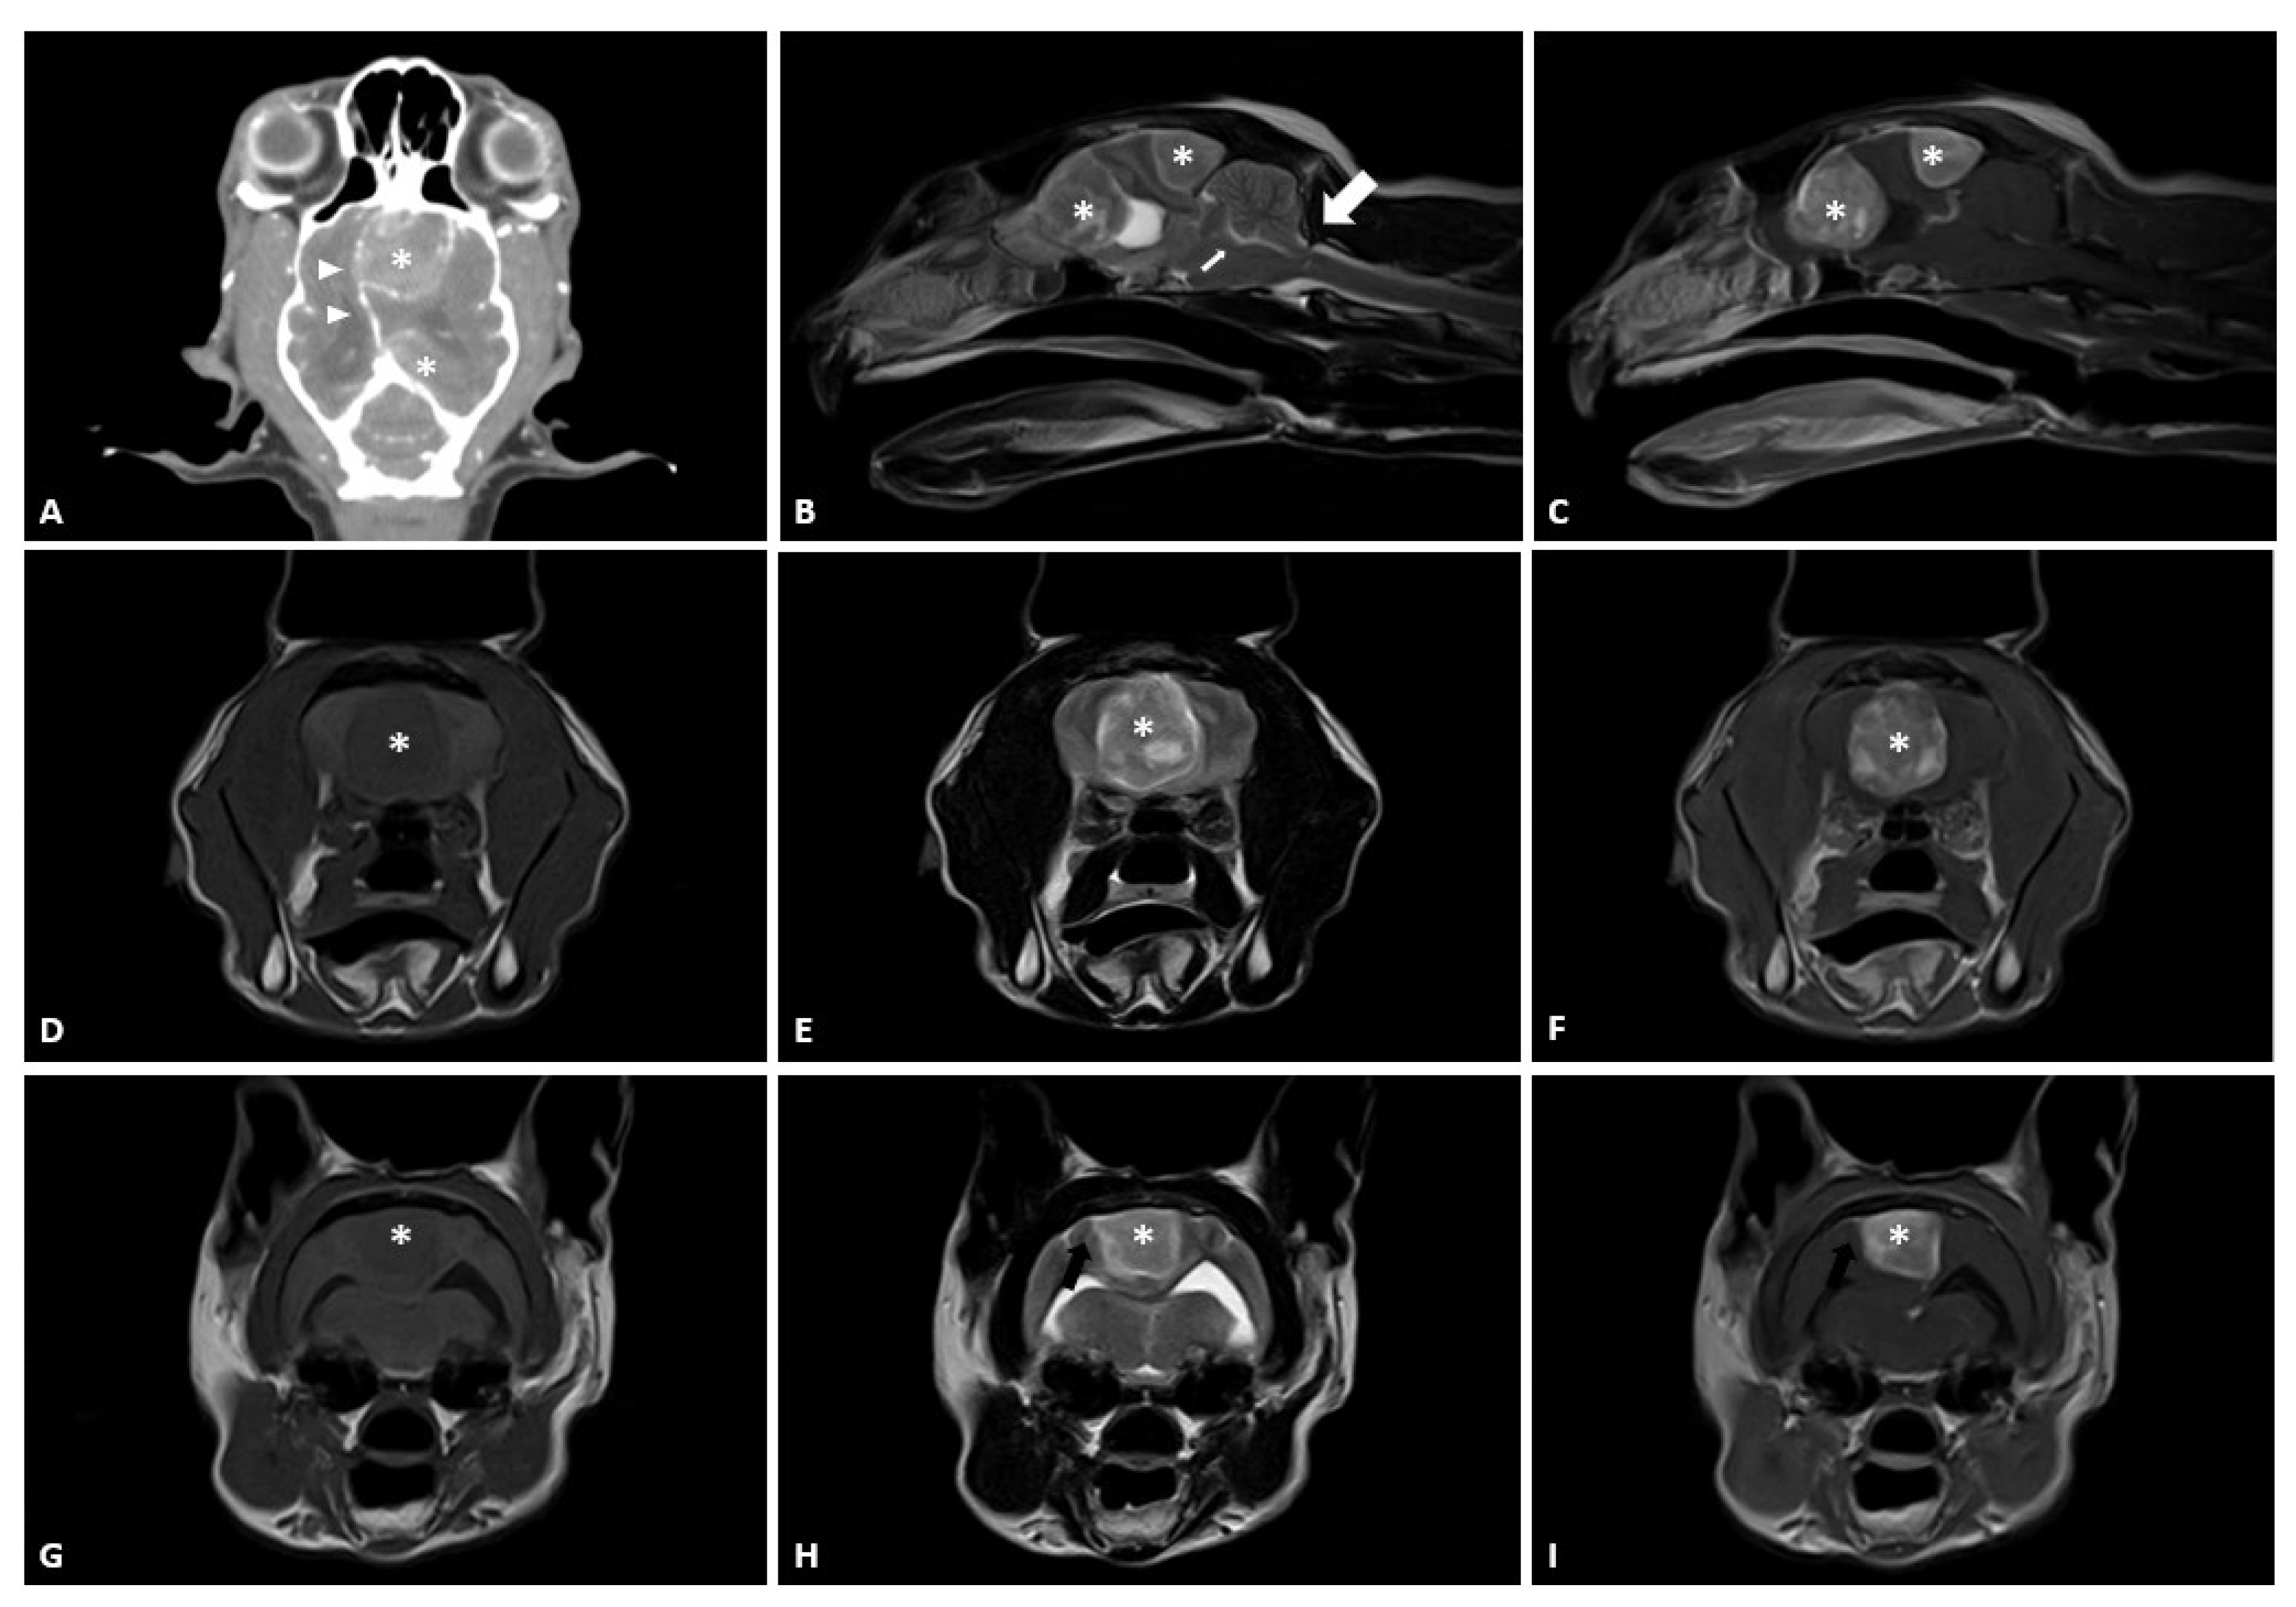

2. Case Presentation

2.1. Case